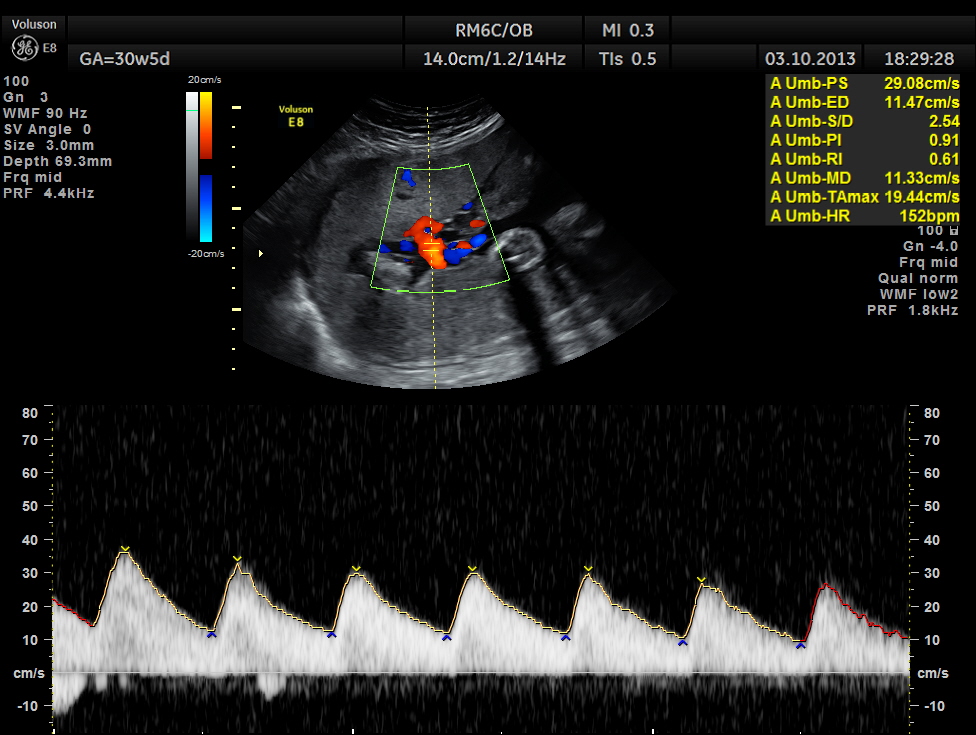

The umbilical artery doppler appeared to be normal. MCA was technically difficult to access.

the umbilical artery doppler appears normal.